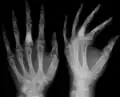

-

X-ray showing calcified enchondromas localized in finger a 37-year-old patient affected with Ollier disease -